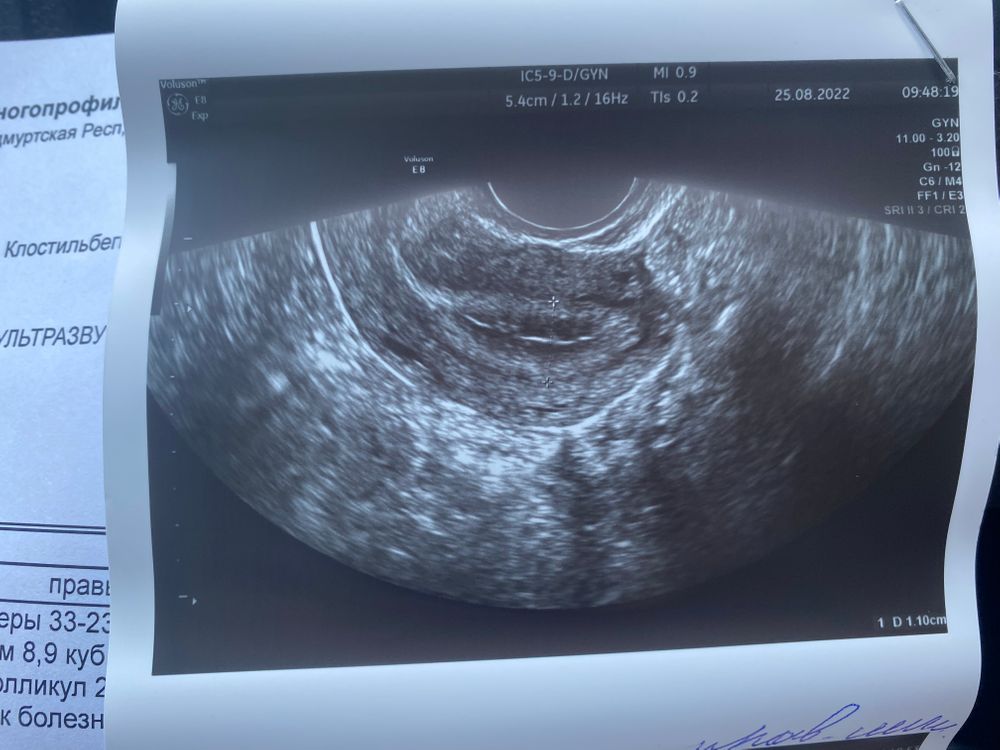

Всем привет, сегодня 18 ДЦ, ранее писала про стимуляцию и овитрель, сегодня была на фолликулометрии мой фолликул так и держится в размерах, 21*14мм, но сегодня она сказала что эндометрий так выглядит как будто овуляция всё-таки произошла, может говорит яйцеклетка вышла и это вовсе не фолликул там сидит, а просто желтое тело осталось, было у кого-то так же?) фото прилагаю

Ольга, А эндометрий это с последнего узи фото, просто он на ней не очень похож на секреторный, у него четко слои просматриваются, я в интернете смотрела фото мэхо второй фазы так он там весь одного цвета без линий, более светлый становится, но я ж не врач, похоже что еще одно узи нужно, что б наверняка, а по БТ вы не следите была или нет овуляция